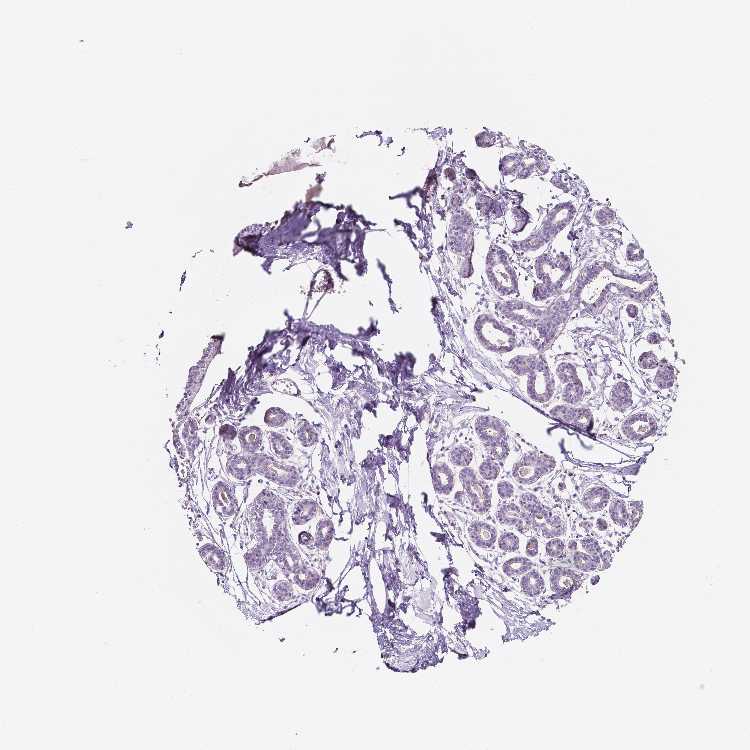

BREAST - Antibody stainingi

Antibody staining in the annotated cell types in the current human tissue is reported as not detected, low, medium, or high, based on conventional immunohistochemistry profiling in selected tissues. This score is based on the combination of the staining intensity and fraction of stained cells.

Each image is clickable and will lead to virtual microscopy that enables deeper exploration of all samples and also displays staining intensity scores, fraction scores and subcellular localization as well as patient and tissue information for each sample.

Antibody HPA001200Antibody HPA018530Antibody CAB000035Antibody CAB068186Antibody CAB073534Antibody CAB080313Antibody CAB080314Antibody CAB080473Antibody CAB080475Antibody CAB080506Antibody CAB080507Antibody CAB080509Antibody CAB080510Antibody CAB080511

Adipocytes Not detectedNot detectedLowNot detectedNot detectedHighMediumLowNot detected-HighNot detectedNot detected-

Glandular cells Not detectedMediumLowNot detectedLowHighNot detectedMediumMediumLowHighLowNot detectedNot detected

Myoepithelial cells Not detectedLowMediumNot detectedNot detectedNot detectedNot detectedMediumNot detectedNot detectedHighNot detectedNot detectedNot detected